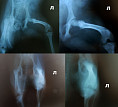

Вот рентгены:

Возможно есть околосуставной перелом по зоне роста...Хорошо бы сделать рентген 2х тазобедренных суставов в хорошем качестве для сравнения, также нужен осмотр лапы на наличие патологической подвижности в коленном суставе...

Вот сделали ещё снимки под наркозом: